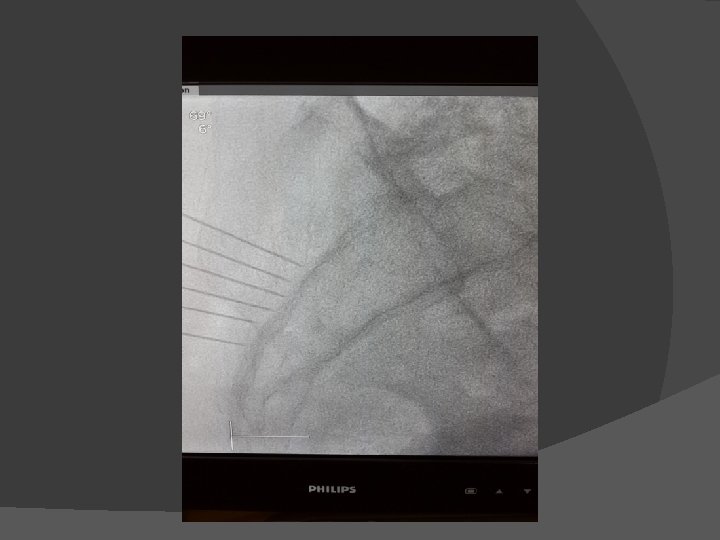

� Kasus 2 wanita 52 th dengan HNP L 4 -5 mengeluh nyeri di punggang bawah menjalar ke kaki kiri selama 1 tahun. DM (+) , HT(+) tidak terkontrol, riw infark miokard 6 bulan yg lalu dengan EF 28%. Menolak untuk dilakukan operasi karena takut akan resikonya. PRF DRG L 5